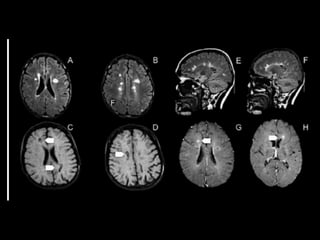

DIAGNÓSTICO   • O  diagnós+co  de  EM  é  complexo,  uma  vez  que  não   existe  marcador  ou  teste  diagnós+co  específico:   diagnós+co  de  exclusão   • Critérios  clínicos  e  radiológicos   • Exames  complementares   – RM   – ESTUDO  DO  LCR   – POTENCIAL  EVOCADO   • vários  modelos  foram  esquema+zados  e  propostos  a   fim  de  orientar  e  facilitar  o  diagnós+co  dessa  doença.     • Atualmente,  os  critérios  de  McDonald,  descritos  em   2001  e  revisados  em  2005,  2010  e  2017,  são  mais   frequentemente  u+lizados

• 41.

• documentação  de  dois  ou  mais  episódios   sintomá+cos,  que  devem  durar  mais  de  24  horas   e  ocorrer  de  forma  dis+nta,  separados  por   período  de  no  mínimo  um  mês   – ou  seja,  disseminados  no  tempo  e  no  espaço   –  Exames  radiológicos  e  laboratoriais,  em  especial  a   ressonância  magné+ca  (RM),  podem,  em  conjunto   com  as  evidências  clínicas,  ser  essenciais  para  compor   o  diagnós+co  e  excluir  outras  doenças  de   apresentação  semelhante

• 42.

Critérios  de  McDonald  revisados  em   2017   • não  são  necessários  exames  adicionais   quando  o  paciente  apresenta  dois  ou  mais   surtos;   •  entretanto,  qualquer  diagnós+co  de  EM  pode   contar  com  RM  e  u+lizar  a  presença  de   bandas  oligoclonais  (imunoglobulina  G  -­‐  IgG)   no  líquor  em  subs+tuição  à  demonstração  de   disseminação  da  doença  no  tempo.

• 43.

critérios  McDonald  (2017)   • disseminação  no  espaço   – RM  por  ≥  1  lesões  hiperintensas  em  T2,   sintomá+cas  ou  assintomá+cas,  que  são   caracterís+cos  de  EM,  em  dois  ou  mais  das   seguintes  quatro  áreas  do  sistema  nervoso   central:     • periventricular,     • cor+cal/justacor+cal,  infratentorial  e  medula  espinhal.

• 45.

• disseminação  no  tempo   – presença  simultânea  de  lesões  captantes  de   gadolíneo  e  lesões  não  captantes  em  qualquer   exame  de  RM,     – ou  nova  lesão  hiperintensa  em  T2  ou  captante  de   gadolínio  quanto  comparada  a  um  exame  de  RM   prévio,  independentemente  do  momento  em  que   foi  realizado.